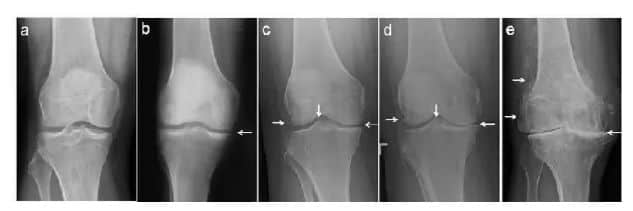

图上可以看到随着时间的推移骨质慢慢增生变形,间隙越来越窄,间隙里是半月板,在x光片下不显影,随着间隙变窄被磨得越来越薄,最后甚至严重到间隙完全消失。

如果出现上述问题,切记及时到医院拍片治疗,早诊断早治疗,后期磨损严重不能行走的时候就要考虑关节置换,莲池骨科小骨为你解答各种膝关节疼痛问题,欢迎在线咨询。